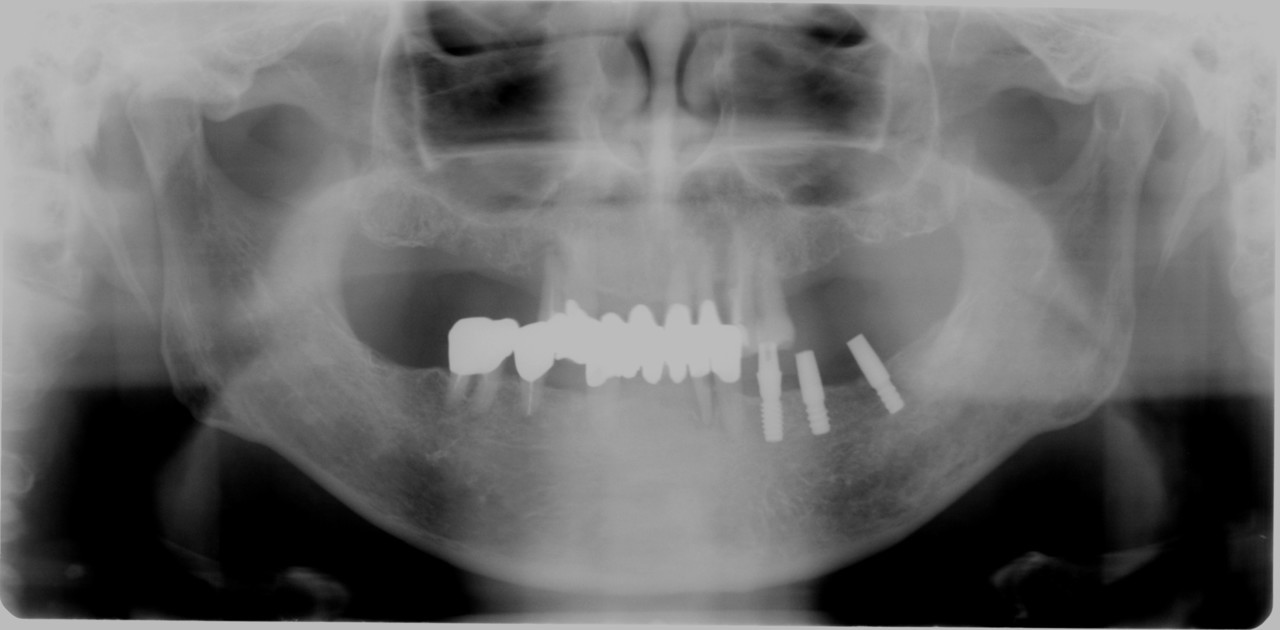

【審美歯科症例ダイレクトボンディング】

■前歯のすき間治療③

【治療前】

正中離開 歯の隙間大きい

【治療後】

費用目安

初診検査料 3,500

期間

2回

合計 33,500+税

2回の来院で治療可能

ダイレクトボンディングのポイント

直接的にセラミック配合された合成樹脂を数層重ねで歯に

接着させる治療方法

●利点

歯を削る事がほとんど無い

痛みがほとんど無い

1ヶ所であれば1日で治療が完了する

●欠点

一生はもたない(2年~5年程度で入れ替え)

過度な使用、歯ぎしりがあると割れることがある